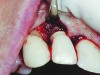

A guided bone regeneration (GBR) approach involving implant surface detoxification (Figure 2), placement of a bone graft combined with a barrier membrane (Figure 3 and Figure 4), and use of a systemic antibiotic has demonstrated the most predictable improvement in peri-implant parameters after destruction of supporting bone. GBR procedures demonstrated reductions in probing depth of 3.16 mm and 2.1 mm of radiographic bone fill in a recent systematic review and meta-analysis of 21 studies by Chan et al.21 Froum and Rosen22 defined a specific protocol based on reentry evaluation of previously treated peri-implantitis sites that included the use of rhPDGF-BB with freeze-dried mineralized bone and the addition of a resorbable membrane. Nonresorbable Gore-Tex® sutures were used to approximate the gingival tissue and were retained in place for 2 weeks. The patient was also kept on chlorhexidine for 2 weeks postoperatively. The reentry photographs from this report are quite impressive. However, the authors do caution the interpretation of re-osseointegration (Figure 5 and Figure 6).

Fig 2. Removal of cement and detoxification with tetracycline hydrochloride.

Figure 2